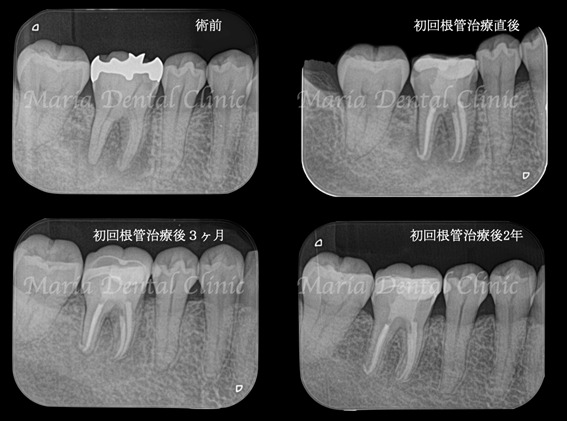

当院の来院時には歯髄反応はすでに失われており、歯髄壊死が起因の根尖性歯周炎であると診断しました。

画像2の赤丸部分には被せ物直下に黒く写る黒い影は2次う蝕(2次カリエス)を強く疑うレントゲン写真でした。

マイクロスコープで治療を開始した際に同部位を確認すると、歯科充填材料の下に広がる虫歯を確認し、通法通りのコンセプトに基づき精密根管治療を施しました。

精密根管治療、初回根管治療の成功率は、歯髄壊死の場合80%〜90%とされており、注意深く予後観察を行なっていく必要があります。

今回は初回根管治療終了後の3ヶ月で骨の再生が始まり、2年後には病変は完全に無くなるまでに回復しました(画像①)。